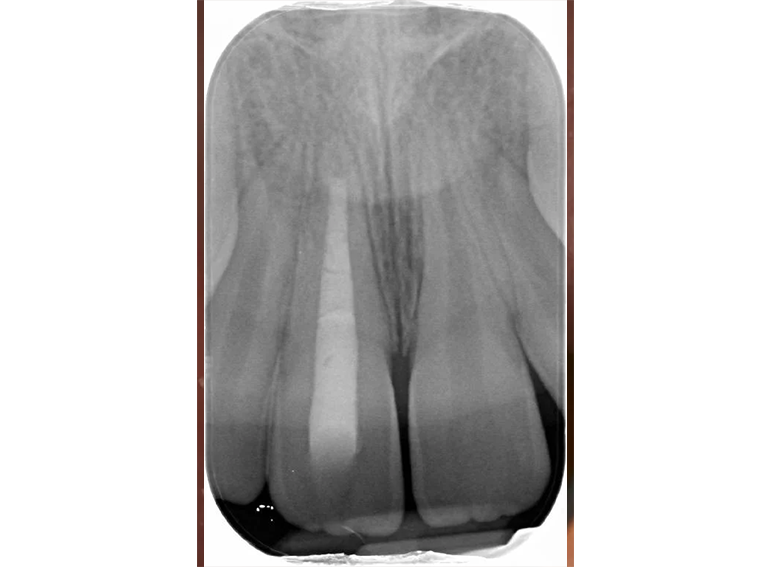

Root filling of an immature tooth and bleaching.